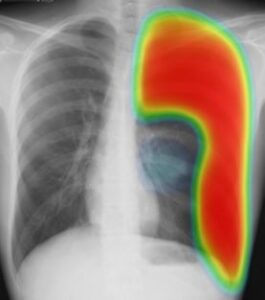

(実際の症例 緊張性気胸 23歳 男性)

突然の左胸痛、進行性の呼吸困難で受診。

胸部X線では、左肺は高度に虚脱し(矢印で囲まれた部位)、左胸腔に溜まった空気が心臓を圧排、心臓が対側に偏位しています。。

低酸素血症もあり、救急車で病院搬送になりました。

左胸腔に溜まった空気に赤い色をつけました